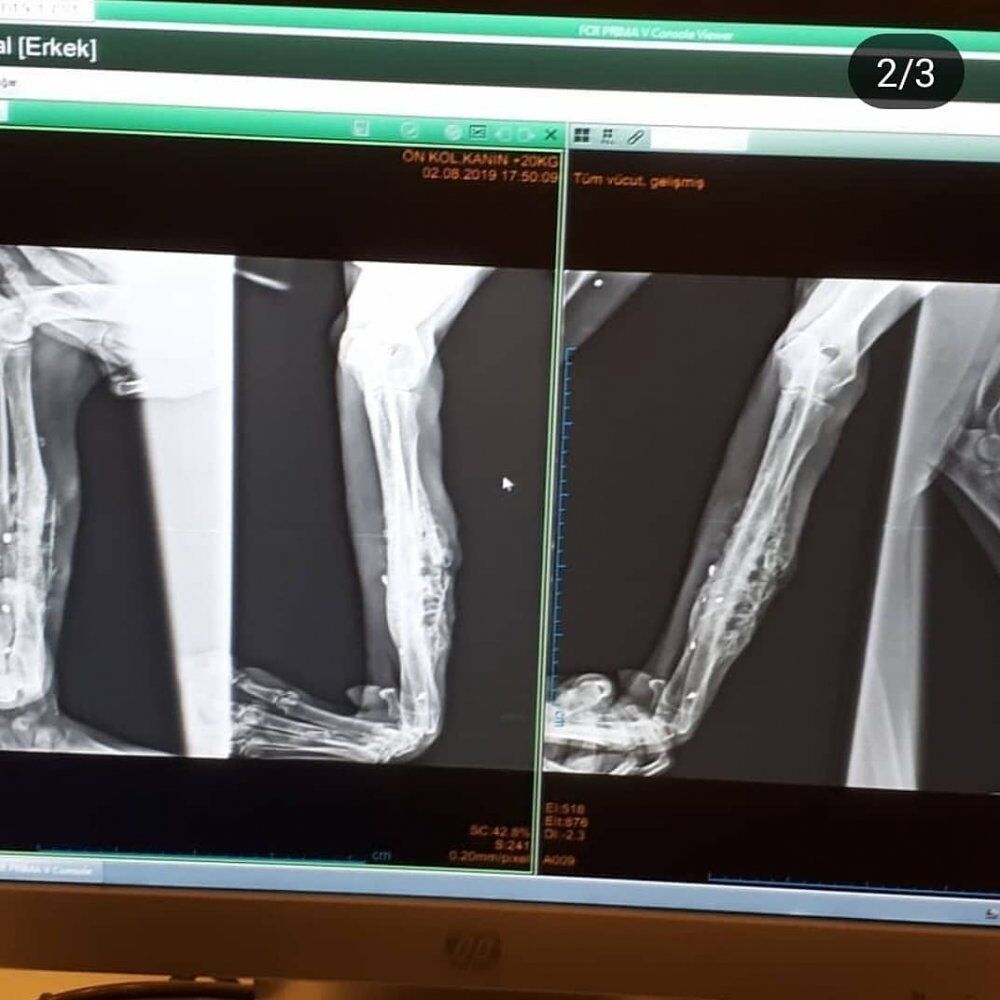

Olayla ilgili edinilen bilgilere göre Erdem Bayram isimli hayvansever ikamet ettiği Çarşamba Havalimanı bölgesinde sokakta sol ön ayağı yaralı bir sokak köpeği buldu. Seke seke gitmekte olan köpeği orada bırakmayarak tedavisi için götürdüğü Samsun 19 Mayıs Üniversitesi Veteriner Fakültesi'nde çekilen film sonucu köpeğin tüfekle vurulduğu, bacağında ise tüfekten çıkan saçmaların kaldığı tespit edildi.

KÖPEĞİN ÇEKİLEN FİLMİ